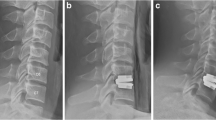

The second generation of the ProDisc called ProDisc-L (Fig. 41.3) is distributed by Synthes (Paoli, Pennsylvania, USA). It was introduced to the market in 2000. Different end plate sizes and lordosis angles, different core heights and only one keel per end plate were the main design changes. It has been approved by the American FDA in August 2006 for one- or two-level implantation. The FDA IDE trial compared the ProDisc II with an anteroposterior fusion using femoral ring allografts anteriorly and pedicle screw fixation with autograft posteriorly. The clinical results in the ProDisc group were slightly better than in the fusion group [35].